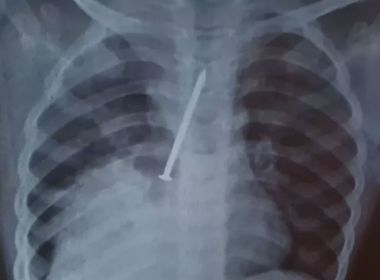

Menino morre após passar 1 ano com prego no pulmão

Uma criança de 3 anos morreu após passar um ano com prego no pulmão. O caso aconteceu no município de…